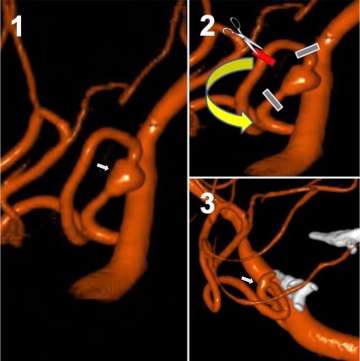

- Microsurgical clipping: In this technique, the neurosurgeon places a titanium clip across the neck/base of the aneurysm to cut off blood flow into the aneurysm, eliminate pressure on the aneurysm, and to prevent rupture. This is technique with excellent long-term outcomes, and it has been continuously refined over the years since its first use in the 1930s (Figure 7).